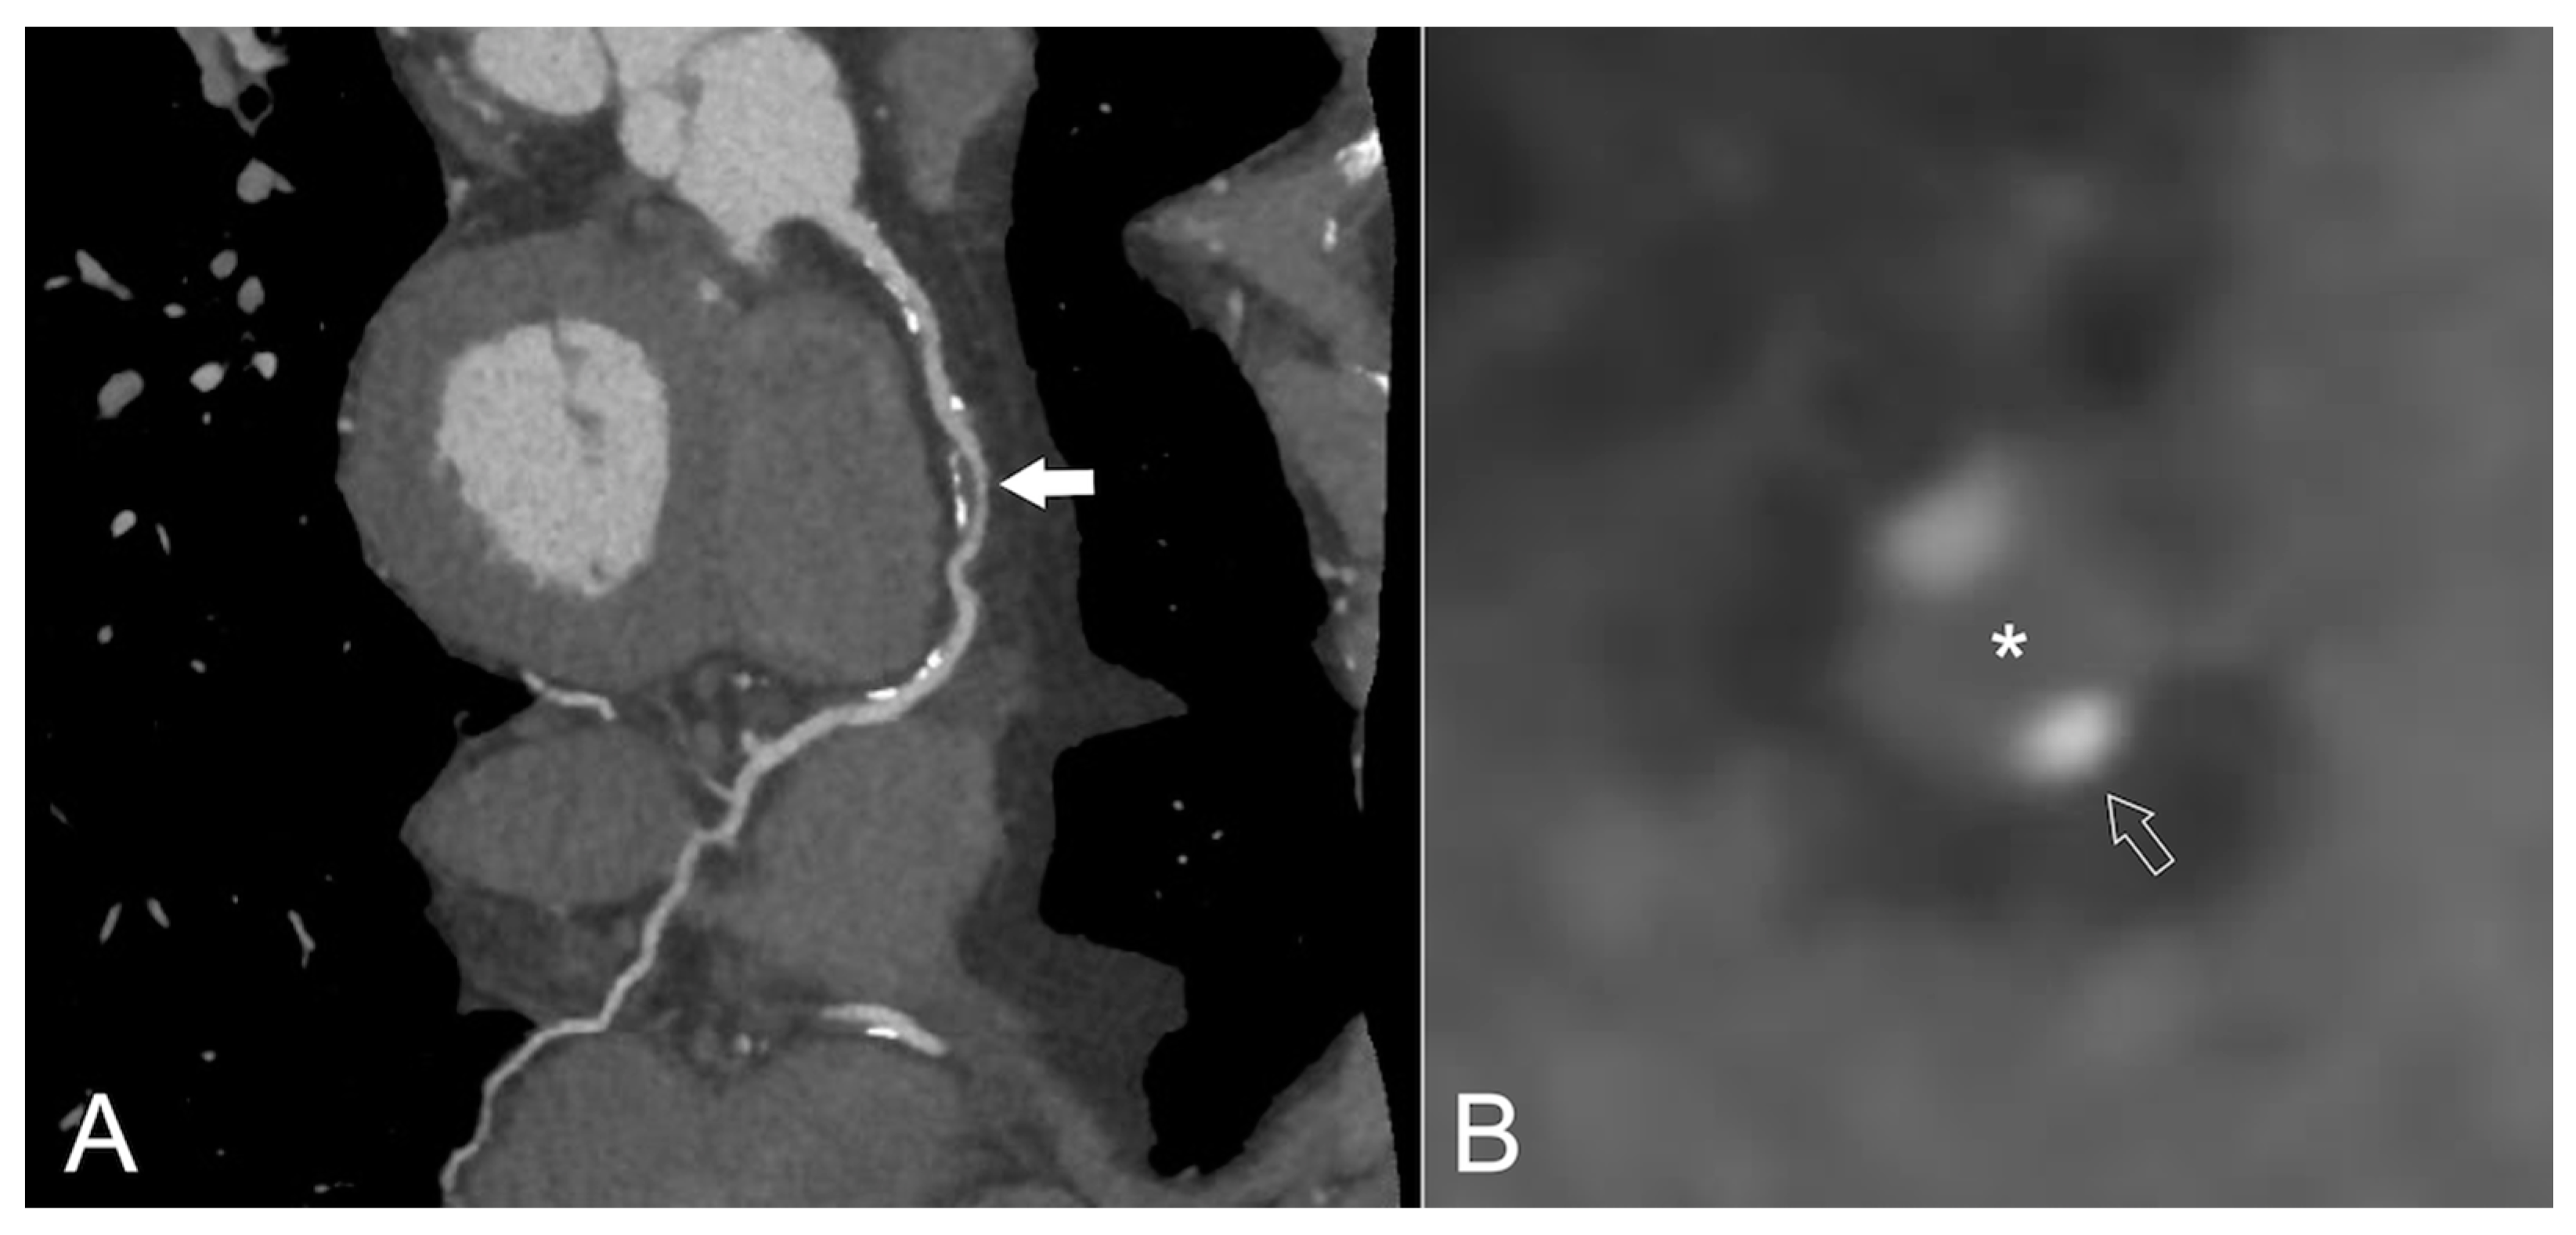

4. Coronary CT Angiography (CCTA)

5. Magnetic Resonance Rmaging (MRI)